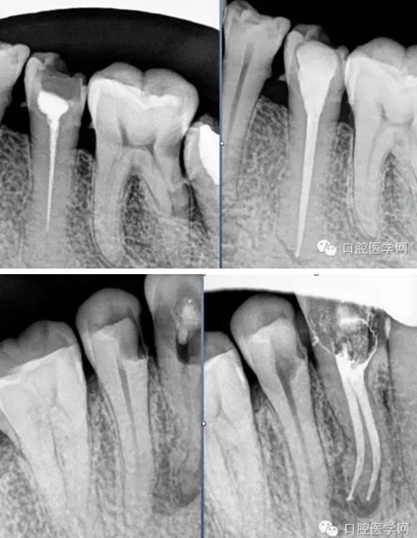

試尖(檢查是否恰填)

根充(從術(shù)后X光片可以看出根管充填完整,專業(yè)上叫恰充)

根充其實(shí)很簡(jiǎn)單,只要前面的預(yù)備做好了,后面的充填就很順利,試尖恰好,AH樹(shù)脂湖劑+大準(zhǔn)度牙膠充填,平齊根管口將牙膠截掉,冷充的話就結(jié)束了。若要做熱充,將攜熱器頭對(duì)準(zhǔn)牙膠的中央,加熱3-4秒迅速壓入需要截?cái)嗟牟课?,然后等十幾秒待攜熱器桿冷卻后再加熱1-2秒取出牙膠,最后將熱牙膠注入,邊注邊壓,嚴(yán)密充填,結(jié)束。暫封一周后冠修復(fù)。通過(guò)這樣的操作牙齒就不可能發(fā)生再次感染和疼痛了。

常用標(biāo)準(zhǔn):恰充,三維致密,流暢,錐度流暢一致。

臨床病例分享:

有什么樣的標(biāo)準(zhǔn)就有什么樣的技術(shù)